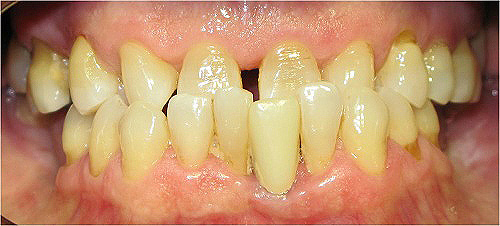

Resultado de colocação de implante dentário na Clínica São Filinto

Caso 8 - Colocação de implantes dentários para reabilitação com prótese fixa em zircónio cerâmica no 4º quadrante.

![]() |